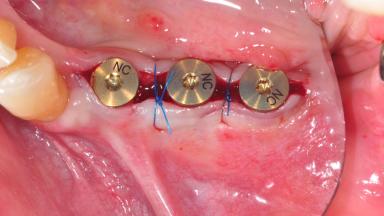

For soft tissue management, the initial healing caps are replaced with a longer type 8 weeks after implant placement in a second intervention before prosthodontic treatment is initiated.